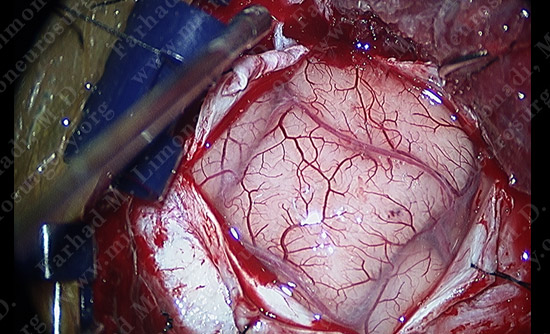

View through the surgical microscope shows the patient’s temporal lobe (brain) exposed. It is time to wake the patient up and proceed with resection of the tumor. It is important to note that the brain does not have pain receptors and the patient will not feel any pain.